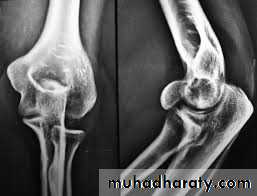

X-RAY:

TI undisplaced vertical split.T2 Displaced single fragment.

T3 comminution.